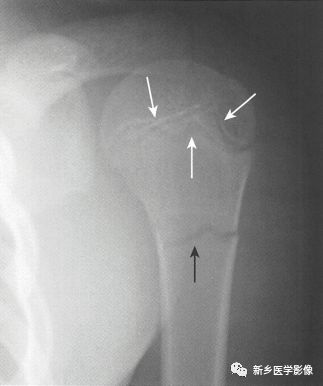

骨折线怎么看图片,跟骨骨折图片怎么看

【图文详解】看不见骨折线的骨折读片口诀

如何识别急性骨折